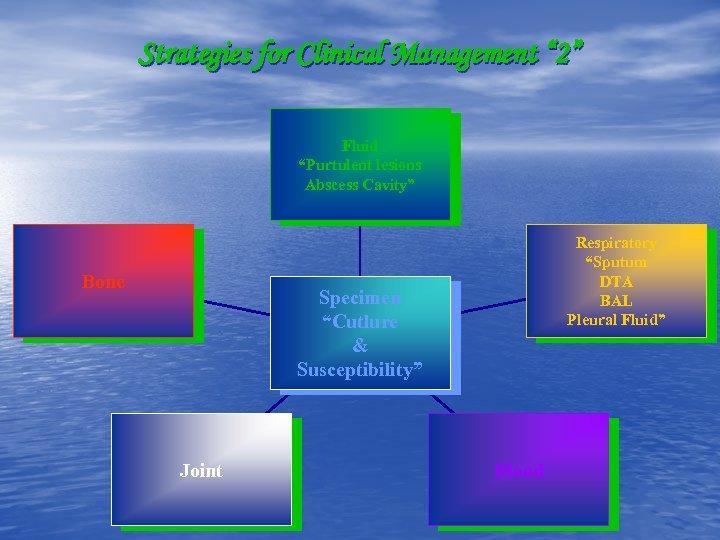

Strategies for Clinical Management “ 2” Fluid “Purtulent lesions Abscess Cavity” Bone Respiratory “Sputum DTA BAL Pleural Fluid” Specimen “Cutlure & Susceptibility” Joint Blood

Strategies for Clinical Management “ 2” Fluid “Purtulent lesions Abscess Cavity” Bone Respiratory “Sputum DTA BAL Pleural Fluid” Specimen “Cutlure & Susceptibility” Joint Blood